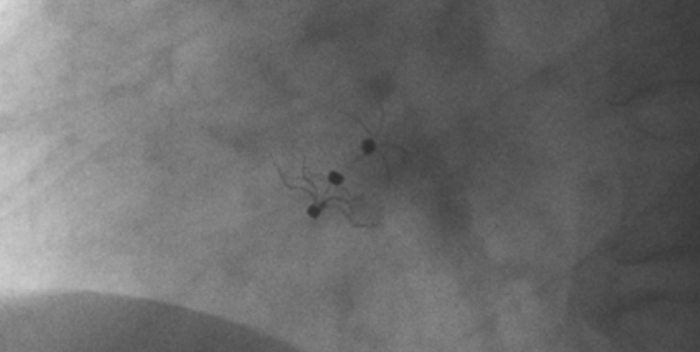

術中造影顯示患者為PFO且長隧道型,目前市場上已商業(yè)化的PFO封堵器難以滿足該患者解剖結構封堵需求。迪創(chuàng)醫(yī)療自主研發(fā)的OmniSeal PFO封堵器自適應性雙盤貼合設計能廣泛適應不同PFO隧道長度的解剖結構和形態(tài),其雙盤外包覆式阻流和隧道內填充阻流相結合的雙重阻流設計,可為此患者實現(xiàn)有效封堵。與此同時,OmniSeal首創(chuàng)的完全可穿刺式設計,也為此患者最大程度地保留了房間隔區(qū)域穿刺通道,以實現(xiàn)全兼容未來可能的左心系統(tǒng)二次介入術。術終造影和心臟超聲顯示封堵完全、效果良好。作為OmniSeal的首例臨床應用,本次手術的順利完成和優(yōu)異效果充分體現(xiàn)了產品的設計創(chuàng)新優(yōu)勢。

影像顯示試驗器械適應性貼合于房間隔兩側且穩(wěn)定